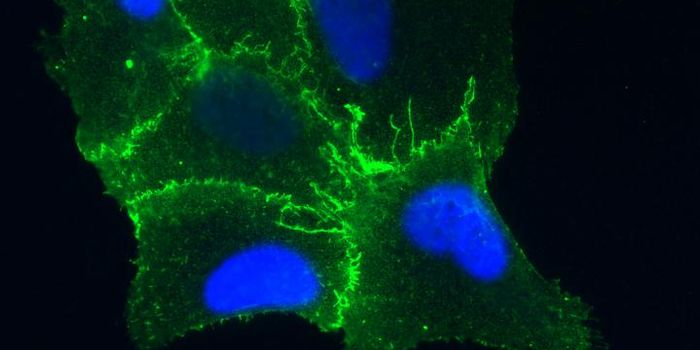

MAR 30, 2016Health & MedicineResearchers claim to have pinpointed the neural stem cells that Zika seems to be targeting. The Zika virus outbrea ...

JUL 29, 2021ImmunologyA developing fetus in its second trimester of life is changing at an extraordinarily rapid pace––bones are b ...